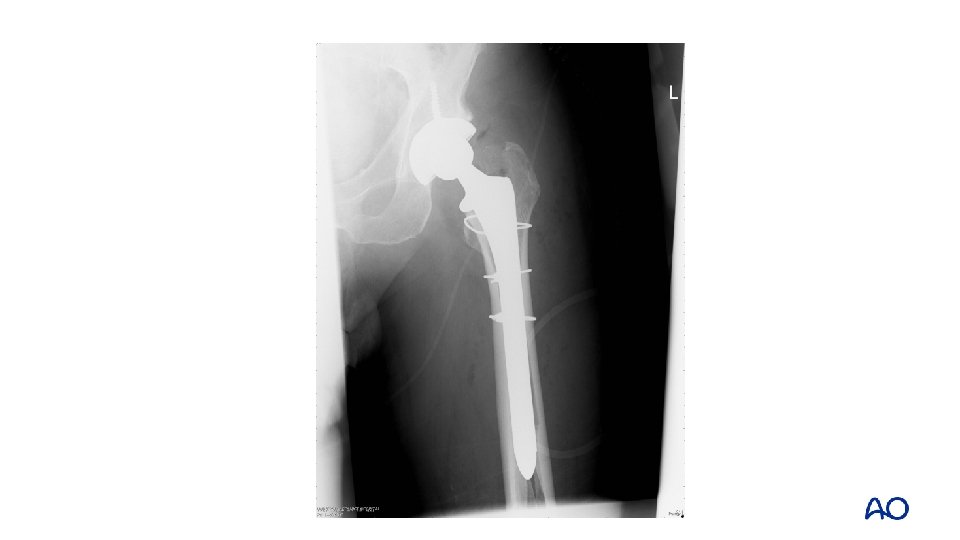

Case 1 • • • Remove stem Prepare distal femur Insert trial stem Insert stem Reduce fracture Definitive fixation

Case 1 • Monoblock stem • Hook plate